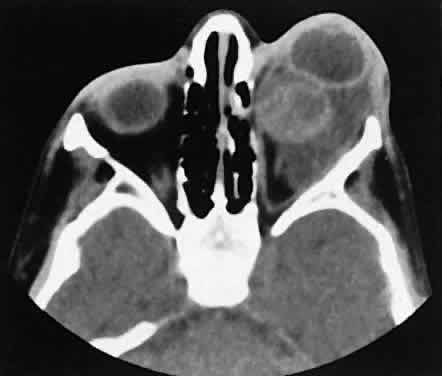

Lymphomatous involvement of the lacrimal gland resembles inflammatory dacryoadenitis radiographically. The enlarged lacrimal gland conforms to the shape of the globe, and the adjacent bone is normal (Fig. 18). We are aware of three high-grade lymphomas that affected the orbit and lacrimal gland and indented the globe, but this is distinctly unusual. Non-Hodgkin's B-cell lymphomas represent the most common type of lymphoma to affect the orbit. Literally any structure in the orbit can be subject to lymphomatous involvement; therefore, a lymphoma should be suspected in the presence of any amorphous isointense infiltrative process.

Fig. 18. Axial (A) and coronal (B) views of lacrimal gland lymphoma. There is homogenous enhancement of the enlarged lacrimal gland. Compared with Fig. 6, there is no difference.